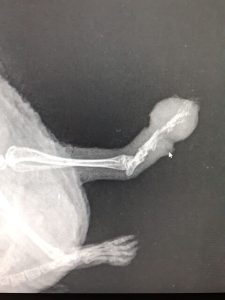

Two hogs have been to the vets this morning with broken hind legs, our vet is going to try and pin them both tomorrow. The first image is a clean